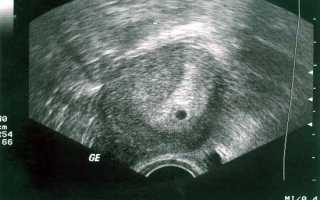

Так выглядит плодное яйцо на сроке 3-4 недели

Плодный мешок, который имеет диаметр всего до 3 мм, датчиком определяется только после 4 недель. А образовавшийся желточный мешок виден специалистам на сроке 5 недель. Когда все явные признаки присутствуют, говорят о наступившей внутриматочной беременности. Практически всегда на этом сроке составляет 5-6 мм, он уже достаточно хорошо визуализируется. Каждый день с пятой по седьмую неделю плодный мешок увеличивается в размерах на 1 мм. Также на пяти неделях уже визуализируется эмбрион, который на тот момент будет иметь размеры около 1-2 мм. Поэтому оплодотворение на УЗИ на ранних сроках визуализировать при наличии можно, но постановка диагноза на сегодняшний день осуществляется другими способами. Основное, на что ориентируются врачи – уровень ХГЧ, но только в крови. Плодное яйцо определяется при ХГЧ, достигающего 1000-2000 мЕд/мл, но рекомендации большинства врачей сводятся к тому, что более-менее безопасное исследование можно проводить, когда уровень ХГЧ превышает 2000 мЕд/мл. Но и это не даст четкой картины о том, как развивается беременность, так как сердцебиение плода можно услышать только тогда, когда его длина достигает 5 мм. Происходит это примерно на 6 или же 7 неделе. В этот срок сердечный ритм соответствует показателям 100 ударов в минуту. Но с увеличением размера плода он учащается до 180 ударов.